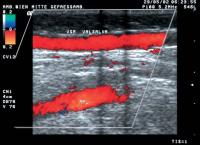

Duplexsonographie - V. poplitea - Thrombose

Abbildung 12: Partielle Thrombose der V. poplitea, erweiterte V. poplitea, Besatz des Lumens mit Binnenechos, Farbkodierung des wandständigen Flusses

Keywords: DuplexsonographieFarbdopplerThrombusVena poplitea